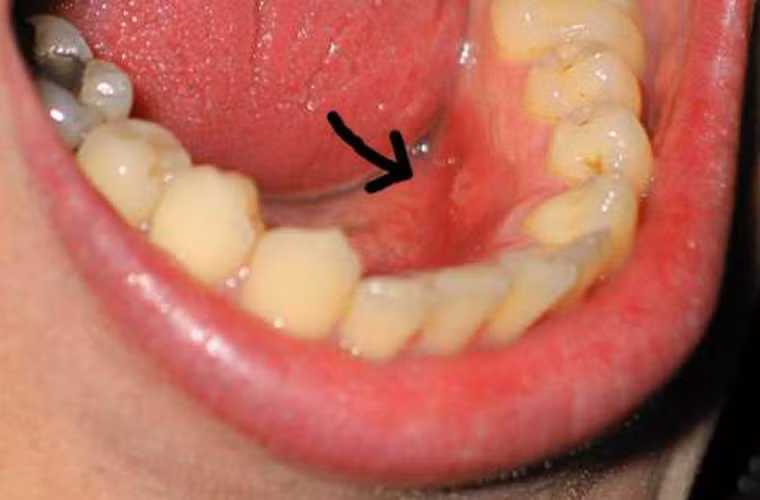

Đi tìm dấu vết khối u. Những khối u này đôi khi không hề mang lại cảm giác đau đớn cho khổ chủ. Chính vì vậy, bạn cần phải đặc biệt chú trọng đến các dấu hiệu như khối u lồi lên với màu nhạt hoặc trắng.

Khi dùng tay kiểm tra, khối u thường được bao quanh bởi một vành cứng. Ngoài ra, nó cũng dễ dàng được nhận diện bởi sự gia tăng về kích cỡ theo thời gian.